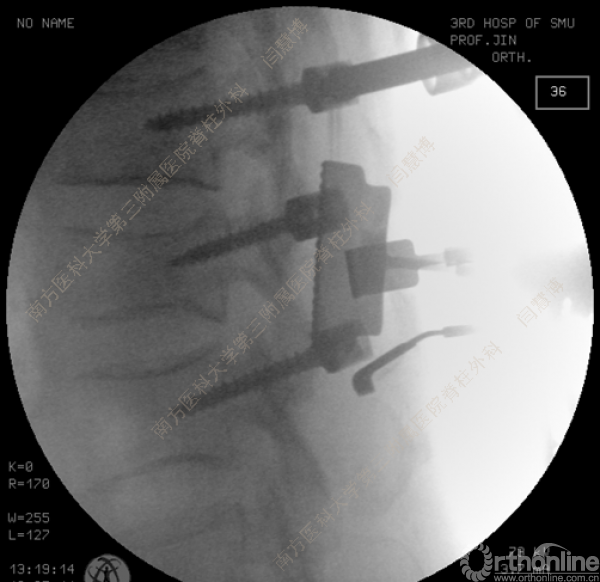

胸腰椎骨折是指由于外力造成胸腰椎骨质连续性的破坏,在如车祸、高处坠落等意外事故中,是最常见的脊柱损伤。老年患者由于本身存在骨质疏松,甚至有可能因为一些如滑倒、跌倒等低暴力因素导致胸腰椎骨折。胸腰椎骨折患者常合并神经功能损伤,且由于致伤因素基本为高能损伤,常合并其他脏器损伤,这为治疗带来了极大的困难和挑战。针对胸腰椎骨折,南方医科大学第三附属医院闫慧博教授介绍了他们运用微创方法治疗的经验。